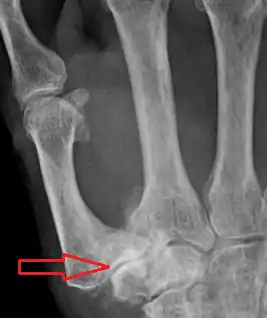

| Osteoarthritis of the first carpometacarpal joint | |

CMC OA can be divided into different stages which show the progression of the disease. The most commonly used classification is the radiological staging protocol according to Eaton and Littler. Four different stages are distinguished on radiological evidence of synovitis, joint space and capsular laxity.[15][21]

Stage 1:

- "synovitis phase"

- slight widening of the joint space

- articular contours are normal

- < 1/3 subluxation of the joint (in any projection)

Stage 2:

- There is a significant capsular laxity

- 1/3 subluxation of the joint

- Osteophytes, < 2 mm in diameter, are present. (usually adjacent to the volar or dorsal facets of the trapezium)

Stage 3:

- > 1/3 subluxation of the joint

- Osteophytes, > 2 mm in diameter, are present (usually adjacent to the volar and dorsal facets of the trapezium)

- Slight joint space narrowing

Stage 4:

- Major subluxation of the joint.

- Very narrow joint space

- Cystic and sclerotic subchondral bone changes are present

- Significant erosion of the scaphotrapezial joint.